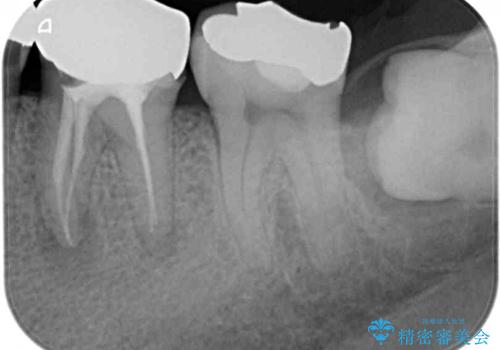

- 根っこの一部だけになった歯と咬むと痛みのある歯を気にして来院された患者様です。

上顎の歯根のみとなった歯は抜歯が必要であったので、抜歯を行い、インプラントあるいはブリッジのよる補綴治療を提案しました。

下顎の根管治療がされた大臼歯は咬合時に痛みが認められたため、再度根管治療を行った後に補綴治療することとしました。